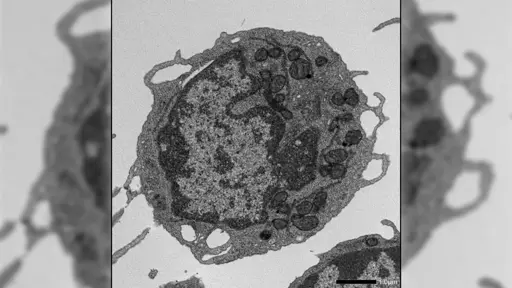

Scientists have discovered that a protein linked to cell death is secretly driving the aging of blood stem cells in a completely different way. Instead of killing the cells, it damages their mitochondria, sapping their energy and weakening the immune system over time. When this protein was turned off, stem cells remained stronger and more balanced, even under stress. The findings point to a new strategy for slowing aging at its source.